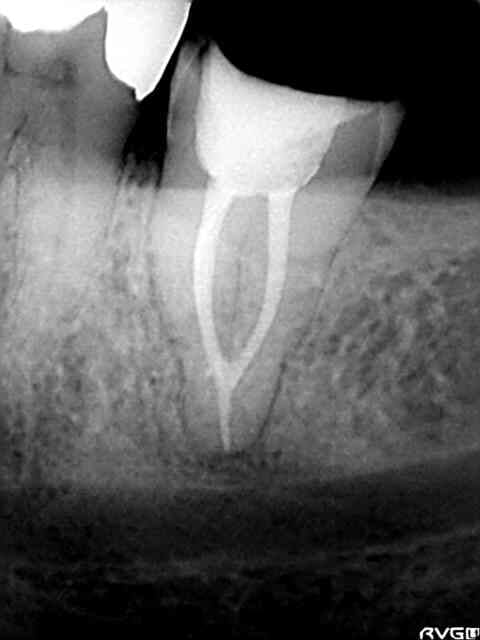

Un cas traite l'an dernier et pas de pb a ce jour ...

Bon déja t as pas chopé le NAI....te plains pas.....

c'est vrai il est pas très loin ....